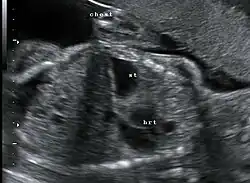

Die angeborene Zwerchfellhernie kann vor der Geburt im Ultraschall ab der 18. SSW dargestellt werden. Wird eine solche Diagnose vorgeburtlich gestellt, sollten weitere Untersuchungen (z. B. Kernspintomographie) in einem spezialisierten Zentrum erfolgen, um das Ausmaß an vorgeburtlicher Lungenschädigung einschätzen zu können, das die Prognose für das Überleben der Kinder und die angestrebte Erstversorgung wesentlich beeinflusst.